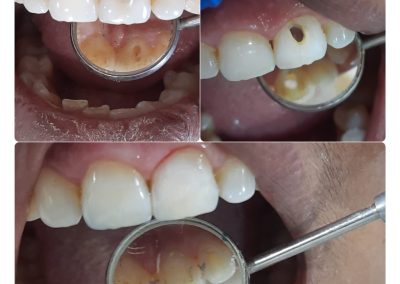

Narayan Multispeciality Dental Clinic